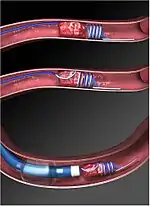

The retriever consists of a long thin wire with a helical coil formed at the distal end. A balloon catheter is snaked into the affected vessel from the femoral artery, and the balloon is inflated to prevent blood flow that could hinder the retrieval process. The retriever is then fed through the catheter, during which the distal coil is straightened to fit through the catheter tube. When the retriever emerges at the clot site, the coil reforms, wrapping around the clot and allowing the clot to be removed with the catheter.[3]